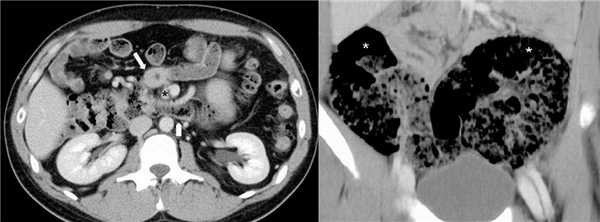

Рисунок. На КТ обратное вращение 12-ти перстной и толстой кишки: 12-ти перстная кишка спереди, а поперечная ободочная кишка сзади от ВБА (звездочка). На втором снимке неполная фиксация печеночного и селезеночного углов ободочной кишки: печеночный и селезеночный углы (звездочки) располагаются в нижнем этаже брюшной полости.

При проведении ирригографии в месте заворота сигмовидной кишки определяется симптом «клюва», над которым кишечник значительно перераздут. По ориентации кончика «клюва» определяют направление перекрута - по часовой стрелке или против. При завороте слепой кишки контраст не проходит далее середины восходящей части ободочной кишки. Наиболее информативным методом исследования является мультисрезовая спиральная компьютерная томография органов брюшной полости. На МСКТ в месте заворота определяется «спираль», петли кишечника расширены, явно визуализируется утолщение стенки кишки и брыжейки за счет отека.